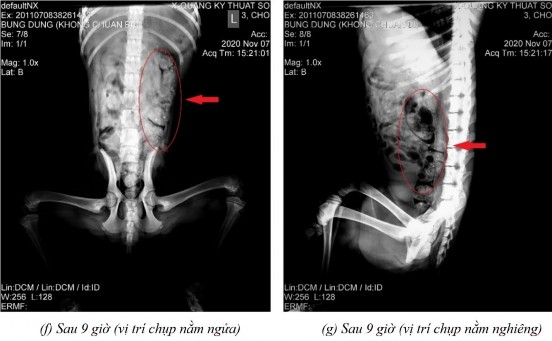

Phụ lục 5.4. Hình ảnh X-quang chó 5 ở thời điểm (a) sau 2 giờ 20 ở vị trí nằm nghiêng, (b) sau 4 giờ ở vị trí nằm ngửa, (c) sau 4 giờ ở vị trí nằm nghiêng, (d) sau 7 giờ ở vị trí nằm ngửa, (e) sau 7 giờ ở vị trí nằm nghiêng, (f) sau 9 giờ ở vị trí nằm ngửa, (g) sau 9 giờ ở vị trí nằm nghiêng, (h) sau 11 giờ 40 ở vị trí nằm ngửa và (i) sau 11 giờ 40 ở vị trí nằm nghiêng